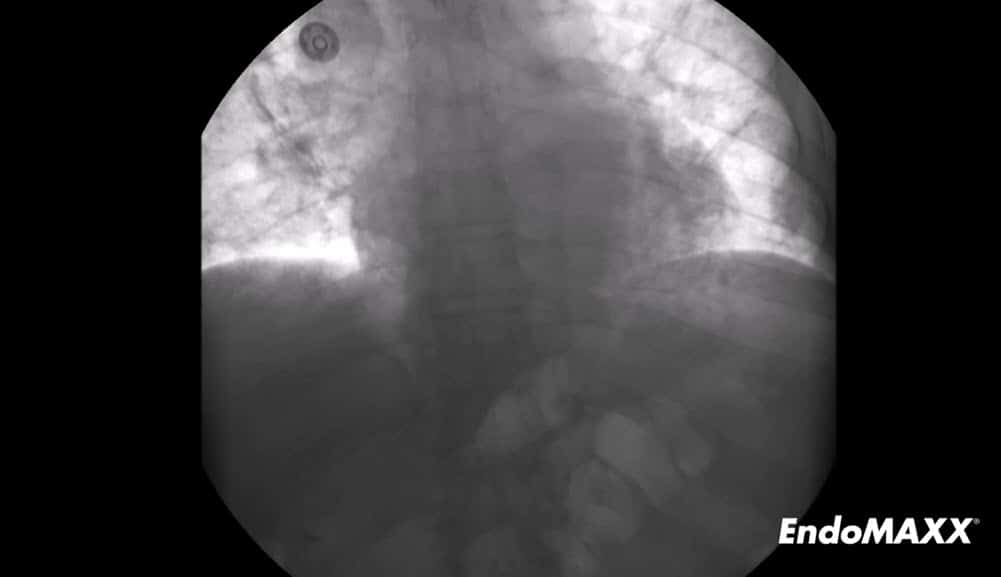

The EndoMAXX fully covered esophageal stent is designed from years of clinical experience and feedback. This stent incorporates advanced features that help alleviate common adverse events associated with esophageal stenting.